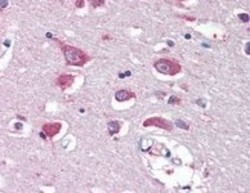

AP16819PU-N IHC

Immunohistochemistry